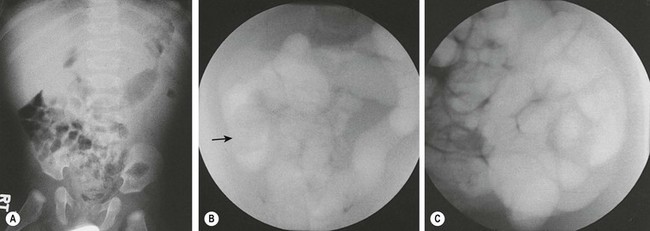

FIGURE 38-8 Plain radiography and fluoroscopic examination using air for pneumatic reduction of an intussusception. (A) Plain radiograph showing a mass effect in the right upper quadrant. (B) Pneumatic reduction to the vicinity of the cecum with the intussusception still present (arrow). (C) Complete reduction with reflux of air into multiple loops of small intestine. (Courtesy of Charles Maxfield, MD.)